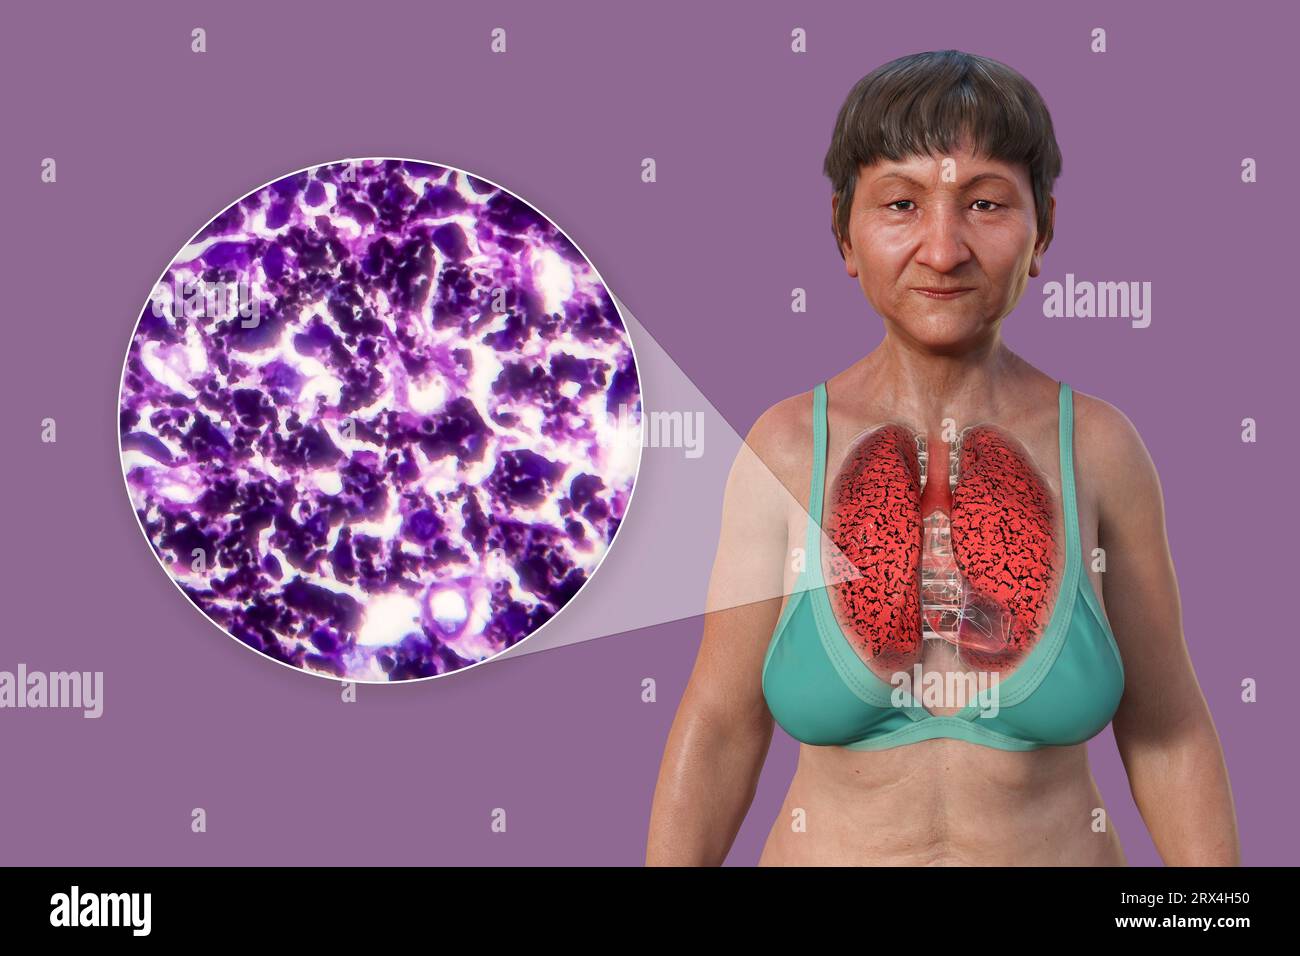

Radio Poumon Fumeur Vs Poumon Sain

Gallery